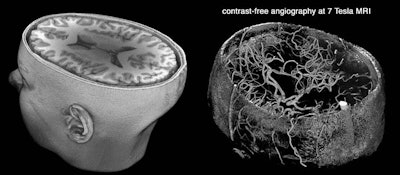

A 3D rendering of a 7-tesla brain MRI scan (left). Time-of-flight MR angiography (right) images blood flow without the need to administer contrast. One of the main applications of 7-tesla MRI is in the diagnosis of intracranial aneurysms. Image courtesy of Dr. Farshid Sepehrband and Arthur Toga, PhD.At the Mayo Clinic, the No. 1 application for 7-tesla MRI is for patients with seizures. In fact, seizure imaging is driving all referrals for 7 tesla, Welker said.

Vascular imaging is also improved for both arteries and veins in terms of blood vessels within the brain. The high-field magnet is "extremely good for sorting out small aneurysms and trying to determine whether an abnormality seen on a 1.5-tesla scanner or a 3-tesla scanner is an aneurysm or not," Welker said.